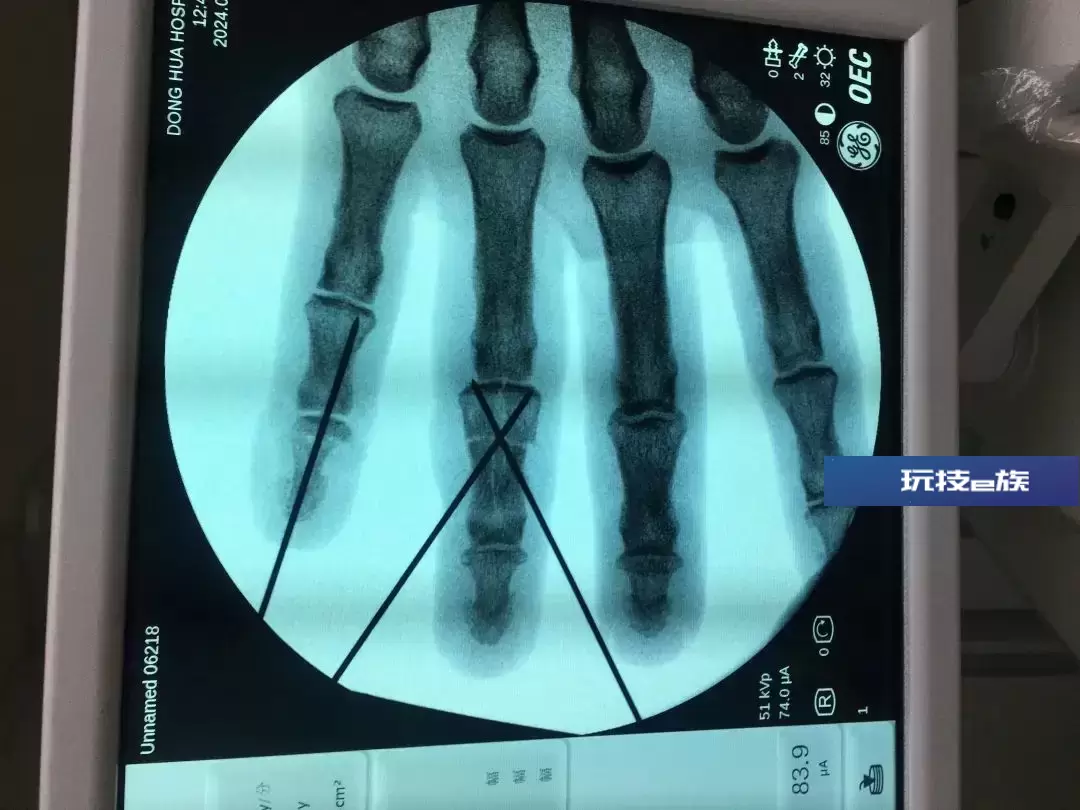

接诊的医生见其左手中环指近指间关节皮肤软组织不规则创口,创缘不齐,环指中末节严重肿胀,中节可及骨擦感,并经X线等专业检查,以左手环指中节开放指骨骨折伴神经血管肌腱损伤等创伤将其收治入院,并与助手孙晓红、尹齐齐立即对其施行手术。

环指掌侧切开,创口内可见中节指骨粉碎骨折、缺损,屈指深肌腱部分断裂,环指双侧指神经及指动脉撕脱断裂、缺损,双侧指动脉栓塞、血栓形成。

根据其环指损伤的具体情况,医生于环指掌侧再作辅助切口,对粉碎骨折的左手环指中节指骨复位后固定,用骨修复材料进行植骨修复,并缝合修复部分断裂的屈指深肌腱。

见双侧指动脉、指神经缺损,血管、神经张力较大不能直接缝合,医生又于前臂掌侧取同等管径皮下静脉1条,分成两段后血管倒置后予以移植。同时于前臂掌侧取皮下神经1条,分成两段后予以移植。